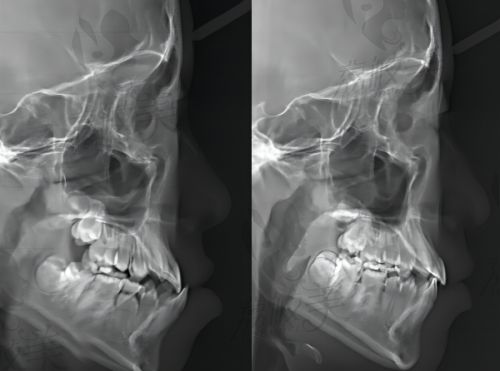

医院配备全景X光、口腔内扫描仪、3D建模系统,可严谨呈现牙体状况。结合爱尔创牙冠的个性高定设计,极大提升了佩戴者的舒适度与美观度。